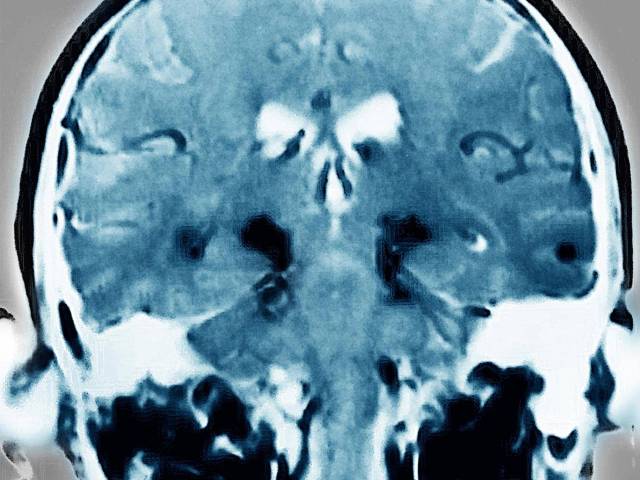

Chụp cộng hưởng từ (MRI) để chẩn đoán xem có mắc bệnh Parkinson hay không. Ảnh: Getty